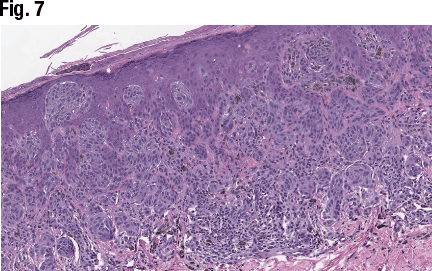

In another case, a 14-year-old female presented with a brown lesion on her right lower abdomen. The asymmetrical but circumscribed proliferation of epithelioid melanocytes is seen in Fig. 6. The cells are arranged with larger nests in the superficial dermis and epidermis (Fig. 7), and Dr. Aung noted the irregularly dispersed pigments and lymphoid aggregates at the base of the lesion. Fig. 8 shows the pagetoid migration of melanocytes at the periphery of the lesion and Kamino bodies, “which are supposed to be seen more frequently in benign [lesions], so this lesion is showing both benign and malignant morphologic features,” she said. In high power (Fig. 9), “this lesion failed to show a maturation pattern.” Some of the lesional cells showed cytologic atypia with pleomorphism, including scattered mitotic figures within the dermis.